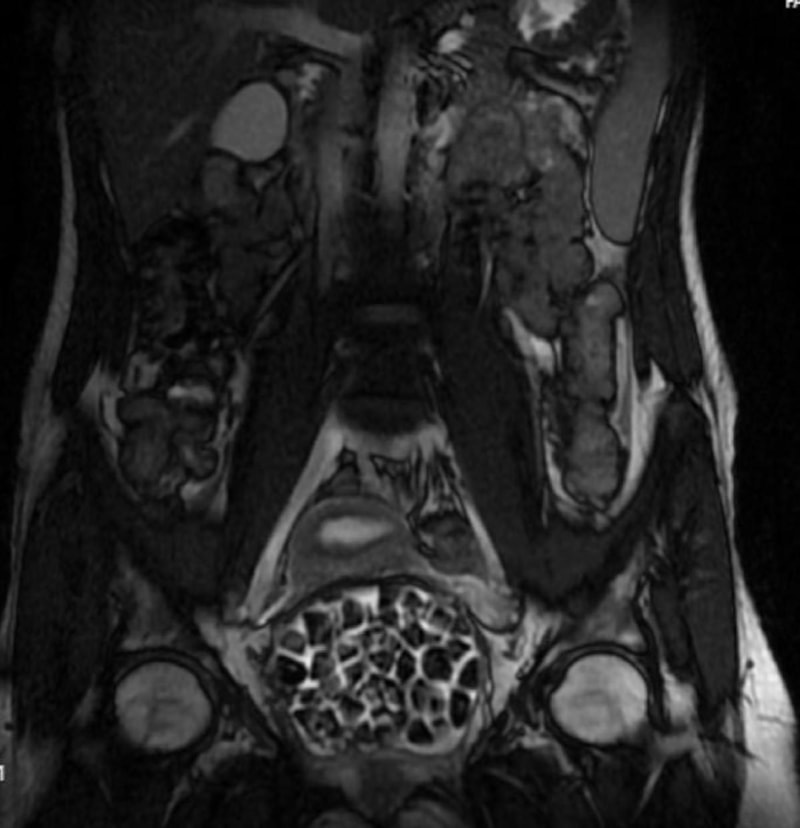

Hastasının durumuna yönelik konuşan Üroloji Uzmanı Doç. Dr. Erkan Erkan, "Hastamızın 2004 yılında doğduğunu ardından doğar doğmaz ekstrofi vezika dediğimiz 50 binde bir görülen bir anomaliden dolayı art arda ameliyatlar geçirdiğini öğrendik. 10 yaşında yine bir ameliyat geçirmişti, gerekli görüntüleme ve tetkiklerimizi yaptırdık. Normalde mesanesinin olması gereken yerin hemen arka kısmında taşlarla dolu bir kese olduğunu gördük, bunun üzerine ek görüntülemeler; MR çektirdik. Hastamız çelişkili açıklamalar almıştı, kendi radyolojik kliniğimiz ve edindiğimiz konsültasyonlarda taşların mesanede değil vajinal boşlukta oluştuğunu düşündük, bir planlama yaptık.

Kadın doğum hocamızın da çabasıyla taşları tamamen temizledik ardından ileride normal bir hayat sürmesi bakımından oraya plastik cerrahi yaptık. 287 adet taş çıkardık, pratikte gerçekten görünce çok şaşırdık çünkü bu aynı zamanda literatürde çok nadir görülen bir olay. Biz ameliyata hazırlanırken de teorik olarak biraz araştırdık. Literatürde gördüğümüz kadarıyla buna benzer bu tanıma uyan bir vaka vardı. Literatürde sanırım yayınlanmış 2’nci vaka olacak. Farkındalık çok önemli, bilinçli bir hastamız vardı. Doğumsal anomaliyle doğan çocuklarımızda ileride bunlara bağlı bazı sıkıntılar çıkabileceğinin öngörülmesi lazım. İlgili tedavilerini alsalar bile düzenli takiplere gelmeleri gerekiyor. İleride eğer dikkat etmezse ki zannetmiyorum, tekrarlayabilir. Bu rahatsızlık ekstrofi vezikal epispadias durumu, çok nadir bir durum." dedi.

Genç kızın uzun süredir devam eden karın ağrısı olduğunu söyleyerek sözlerine başlayan Jinekolojik Onkoloji Uzmanı Op. Dr. Emin Erhan Dönmez, "Mesane taşları olduğu düşünülerek daha büyük bir hastaneye refere edilmiş. Aramızda mini bir konsey yaparak muayene ettik. Vajen bir hazne görevi görerek orada durağan bir idrar, uzun süre beklediği için idrar içindeki minerallerde çökerek taşlar oluşmuş. Mesanedeki idrarın vajene akmış olabileceği ve vajende göllenen idrar nedeniyle taşların burada oluşacağını düşündük, ameliyatımızı planladık. Ameliyata tanı amaçlı girmiştik, sistoskopi (Mesane gibi idrar yollarını kapsayan kısımlardaki rahatsızlıkların teşhis ve tedavisinde kullanılan endoskopik bir yöntem) dediğimiz ameliyatı Erkan Hocam ile birlikte gerçekleştirdik.

Önce mesaneyi bir görüntüledik, mesane tabanına yaklaşık 2-3 cm’lik bir alandan vajene fistülize olduğunu gördük. Mesaneden vajene geçtiğimiz esnada tüm vajenin taşlarla dolu olduğunu gördük. Tanı amacıyla girdiğimiz ameliyatta her şey de olağan gittiği için tedaviye geçtik. Taşların çıkabileceği kadar bir genişlik sağladık. Daha sonra yaklaşık en büyüğü 2,5 cm boyutlarında olan, irili ufaklı 287 tane taşı ameliyat esnasında çıkarmış olduk. Taşların tekrarlamaması için idrarın göllenmemesi, en azından dışarıya rahatça boşalabilmesi için vajinal rekonstrüksiyonu sağladık. Ameliyatta da herhangi bir problem yaşamadık. Literatürü Erkan Hocam ile birlikte değerlendirmiştik. Primer olarak vajende birikmiş olan bu kadar çok sayıda taşla ilgili bir makale görmedik, rastlamadık." dedi.